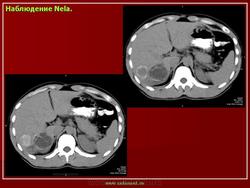

Наблюдение Аманбаева Г.Т.